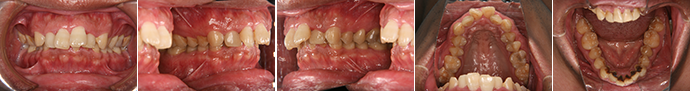

| 主訴 | 噛み合わせが逆、八重歯 |

| 年齢・性別 | 20歳 / 女性 |

| 治療方針 | オトガイの突出感が強く、顔貌改善には外科矯正の方がベストだが本人が希望しなかったため、マルチブラケット装置のみで治療を行った。 |

| 抜歯部位 | 上下顎左右小臼歯(計4本) 治療後に下顎左右第3大臼歯(親知らず) |

| 使用装置 | マルチブラケット装置 |

| 治療期間 | 27か月 |

| リテーナー | 上顎インビジブル、下顎スプリングリテーナー |

| 費用 | 825,000円(税別) |